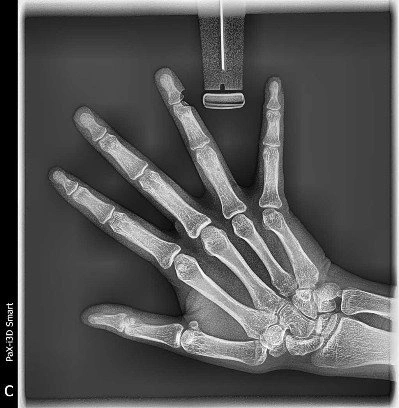

МСКТ кисти

Показания для проведения мультиспиральной компьютерной томографии кисти:

• травмы костей  кисти, запястья, дистальных отделов лучевой, локтевой кости

• дислокации в суставах кисти

• дегенеративные изменения в суставах кисти (артрозы)

• воспалительные изменения в суставах кисти различного генеза (артриты), в том числе, и связанные с системными заболеваниями соединительной ткани (ревматоидный артрит, СКВ и т.д.)

• диагностика причины двигательных нарушений в кисти

• необходимость верификации диагноза при отсутствии определенности при проведении других методов исследования

• планирование и контроль результатов оперативного  лечения (реконструктивных операций)

МСКТ кисти выявляет

Мультиспиральная компьютерная томография выявляет все возможные патологии суставов, костей и мягких тканей (сосуды, мышцы, сухожилья). Врач может выдать направление на данное исследование в случае подозрений на следующие заболевания: артриты, артрозы суставов, опухоли, а также механические и прочие поражения кисти.